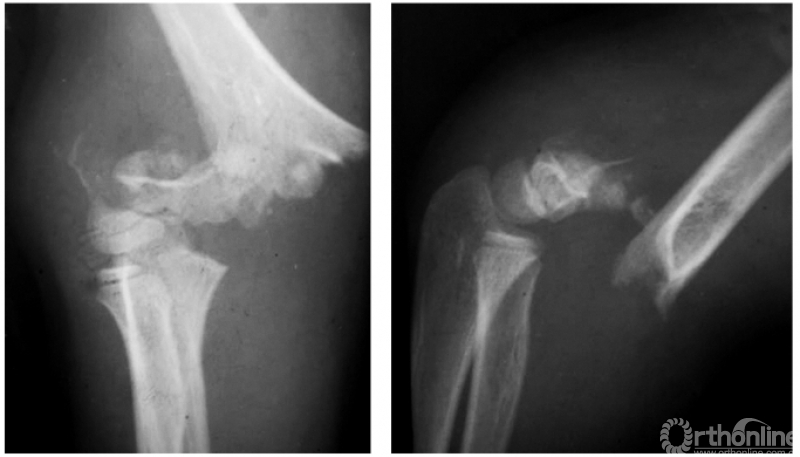

(二) 伸展型

例1:伸展型兼桡偏,即远折端向后向外移位(图2)。

图2

例2:伸展型兼尺偏,即远折端向后、向内移位(图3)。

图3